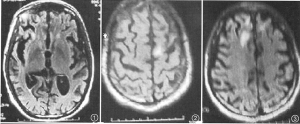

血管神經梅毒的影像學檢查:腦CT示病變腦組織單個或數個較小的低密度梗死灶。腦血管造影可見受累的腦動脈呈彌散性不規則的狹窄,提示在一定距離內血管內膜有炎性增殖

以下檢查有鑑別診斷意義:CT、MRI檢查;腦電圖;顱底攝片;眼底檢查。